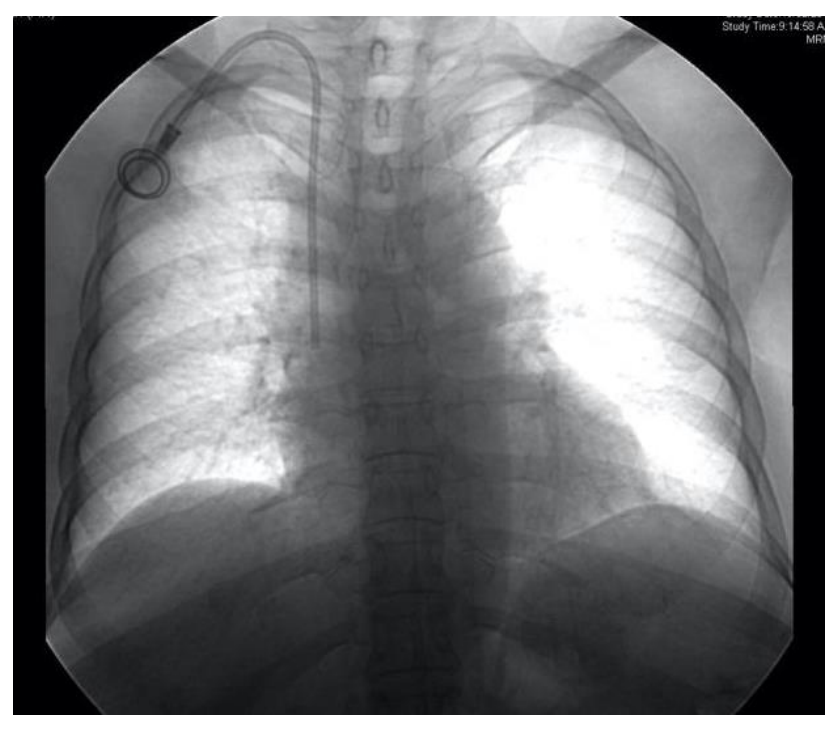

Postprocedure fluoroscopy image or chest radiograph was routinely taken to reconfirm the position and to look for any kinks or migration (Figure 2). The sutures were removed after 10 days in the ward or the IR suite. The chemoports were flushed with heparinized saline after each cycle of chemotherapy.